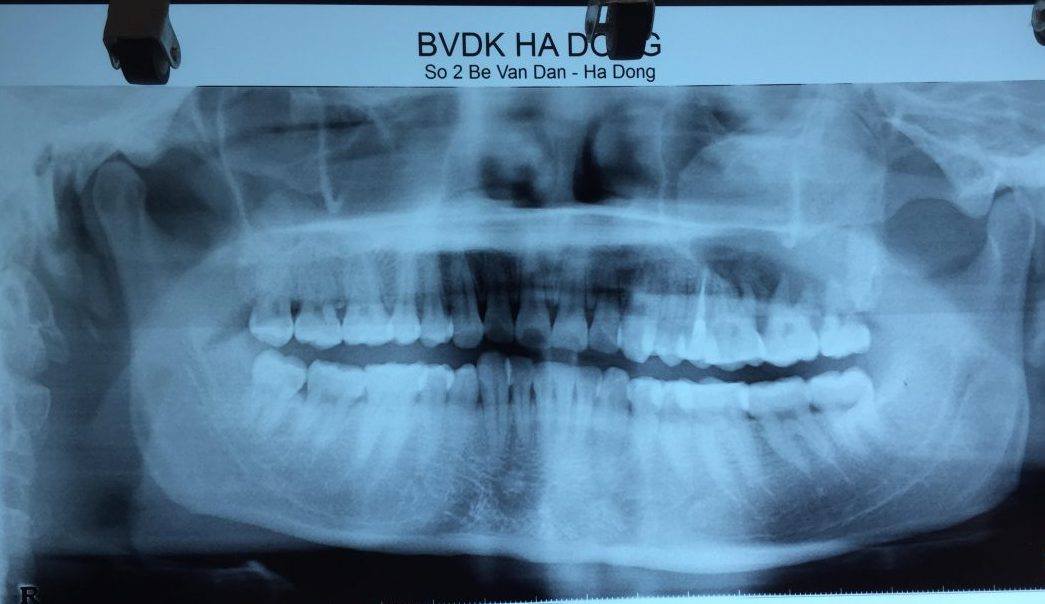

Hình ảnh chụp XQuang hàm mặt 2 tư thế của bệnh nhân Trần văn Cường

Sau 6 tháng, anh Cường nhận thấy khối u tiến triển, vùng hàm bên trái sưng to rõ rệt so với bên phải, nên đã vào Bệnh viện đa khoa Hà Đông. Tại đây khi thăm khám toàn diện, các bác sĩ chỉ định cho bệnh nhân đi chụp X Quang và CT, phát hiện có 1 khối u xâm lấn toàn bộ xương hàm bên trái. Tiến hành phẫu thuật sinh thiết, các bác sĩ đã chẩn đoán bệnh nhân mắc chứng loạn sản xơ xương thể đa ổ. Loạn sản xơ xương là bệnh lý xương mạn tính lành tính không di truyền, trong đó mô xương lành bị thay thế bằng mô xơ.